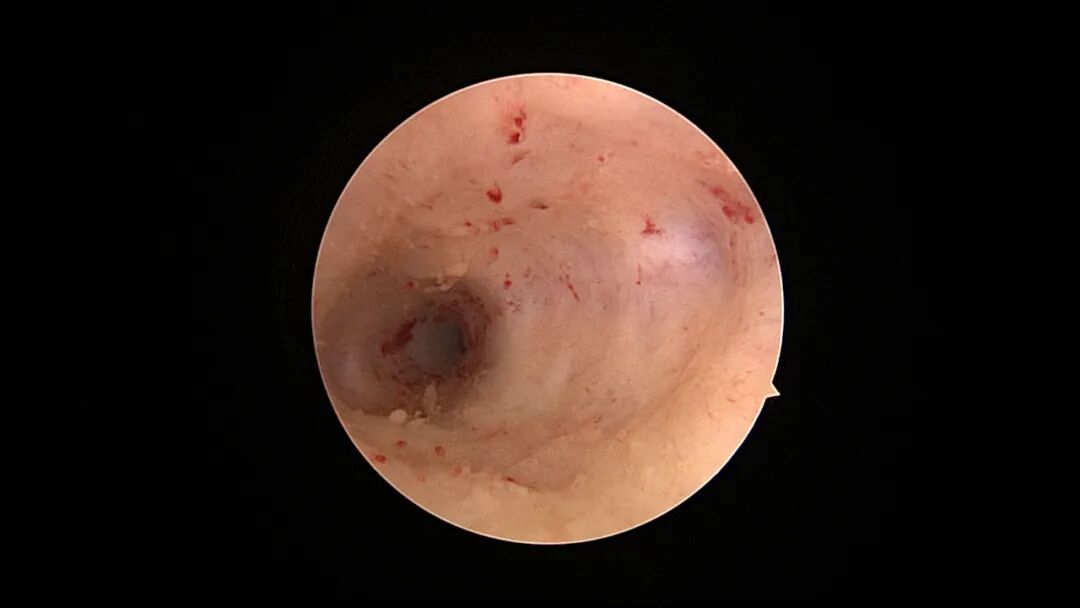

病例1:51岁,G3P1,顺产1次。近半年月经紊乱,周期1~3个月,既往月经规律,偶有痛经。月经前4天B超宫内膜厚0.3cm(双层),月经周期第8天宫腔镜探查,宫颈管及宫腔大量绒毛状息肉,病检为增殖期样子宫内膜。 | ||||